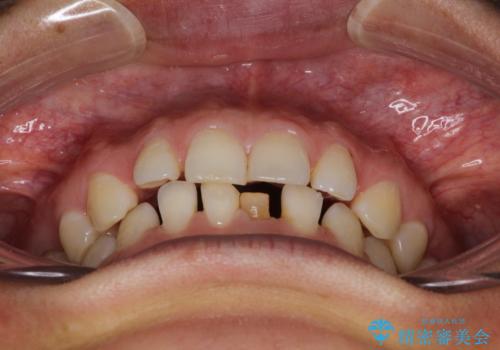

【空隙歯列】ワイヤー矯正で短期間に治療を終えたい

- 歯と歯の間に隙間があることを主訴に来院されました。

下顎前歯は矯正後補綴治療を行なっております。